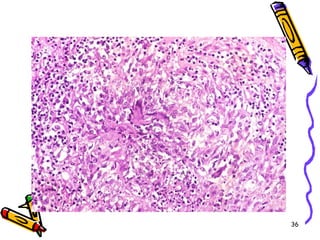

POLİARTERİTİS

• PAN, küçük ve orta büyüklükteki arterlerin

transmural nekrotik iltihabı ile giden

sistemik bir vaskülit

• Özellikle muskuler arterlerin dallanma

noktalarını tutar

• Tutulum, fokal, dağınık ve epizodik

• Lezyonların yaşı değişken

• Genç erişkin hastalığı

Mikroskopi

• Lezyonlar keskin sınırlı ve segmentaldir

• Fibrinoid nekrozla birlikte lökositik

inflamasyon ve tromboz

• İnflamasyon nedeni ile duvarda zayıflama

ve anevrizmal dilatasyon

• Damarın beslediği dokularda infarktüs,

atrofi, hemoraji